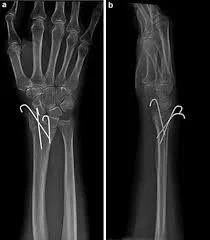

🔹 الشد المفتوح والتثبيت الداخلي باستخدام البراغي والصفائح المعدنية للبالغين (Open reduction and internal fixation)، أما للأطفال تستخدم أسياخ تسمى "K wire”.

🔹 التثبيت الخارجي (External fixation):

يستخدم في حال وجود تهتك كبير بأنسجة العظم والجلد، يتم زراعة مسامير فوق وتحت خط الكسر، ومن ثم ربط أطراف المسامير الخارجية بدعامات خاصة. يساعد هذا الهيكل على تثبيت القطع المكسورة حتى اكتمال التئام الكسور ثم يتم إجراء التثبيت الداخلي بالشرائح.